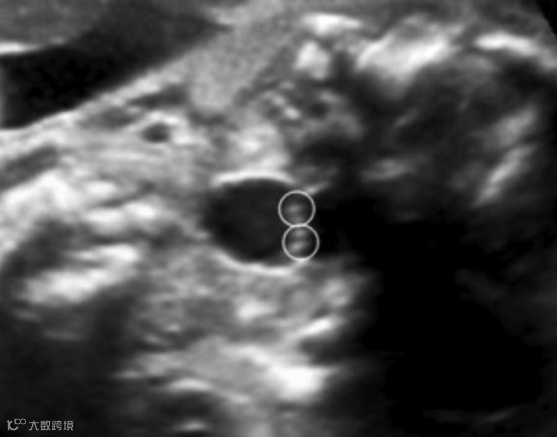

3.软腭如果异常,再往前看硬腭线,由此确定单纯腭裂的程度。

完整的硬腭线

下图可见硬腭线回声中断:

上述几个切面,最容易扫描的是硬腭线,常常作为筛查严重单纯腭裂的平面。